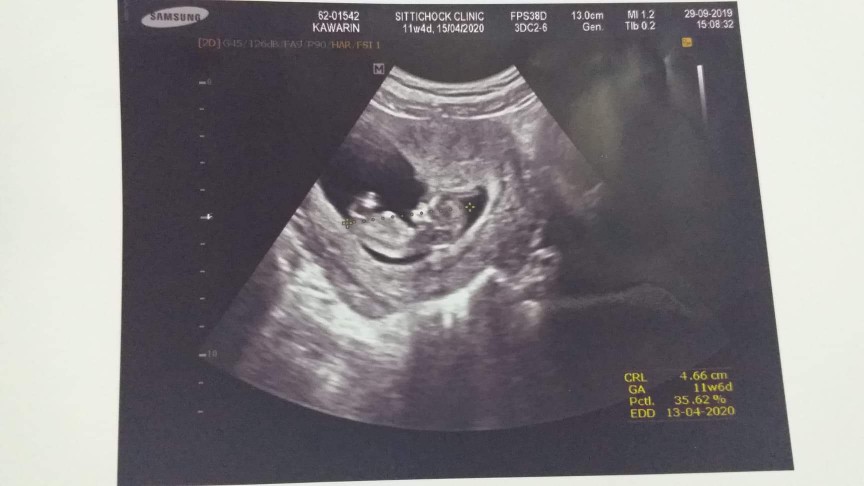

ตอน 10w 4d ค่ะ